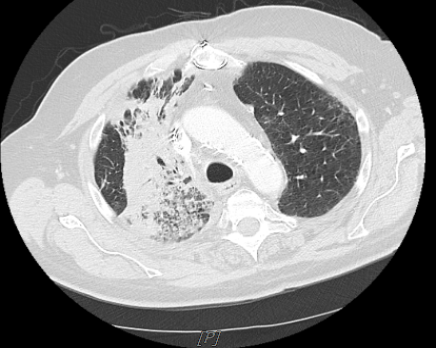

Treatment and management. The patient underwent radiation therapy with a prescription dose of 66 Gy in 33 fractions. Chemotherapy was started with carboplatin and paclitaxel for 6 weeks. One month after treatment, a restaging workup showed a near-complete response, with the disappearance of the right hilar mass (Figure 2). The patient was then started on maintenance immunotherapy with checkpoint inhibitor Durvalumab. The dosage for durvalumab is calculated based on patient body weight. For non-small cell lung cancer, the dosage is 10 mg/kg IV for 60 minutes every 2 weeks or as a consultant oncologist deems necessary.

Figure 2. Chest CT, 1 month after finishing chemotherapy, showing near complete resolution of the mass.

Figure 3. Chest CT after five cycles of Durvalumab showing a reappearance of RUL consolidation with air bronchograms.

Outcome and follow-up. In this case, the patient initially presented with hemoptysis and intermittent shortness of breath and was treated for NSCLC. Four months later, the patient presented again with an area of pneumonitis corresponding to fields of previous irradiation after being treated with durvalumab. Since RRP may mimic cancer progression or pneumonia, bronchoscopy ruled out both causes. Coupled with CT scan findings, it was therefore concluded that the pneumonitis was RRP induced by durvalumab. Systemic steroids and withdrawal of durvalumab promptly improved RRP with durable shrinkage in mass. The patient was started on high-dose steroids, and treatment with durvalumab was discontinued. Within days, the patient demonstrated symptomatic improvement and significant decrease in RUL consolidation.